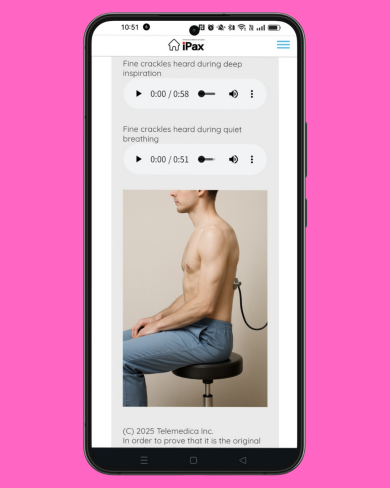

June 18 – Question on Crackles Today’s question focuses on crackles. The question includes a description of the characteristics of the crackling sound. Please listen to the two MP3 audio files and choose the one that matches the description. (June 18, 2025)